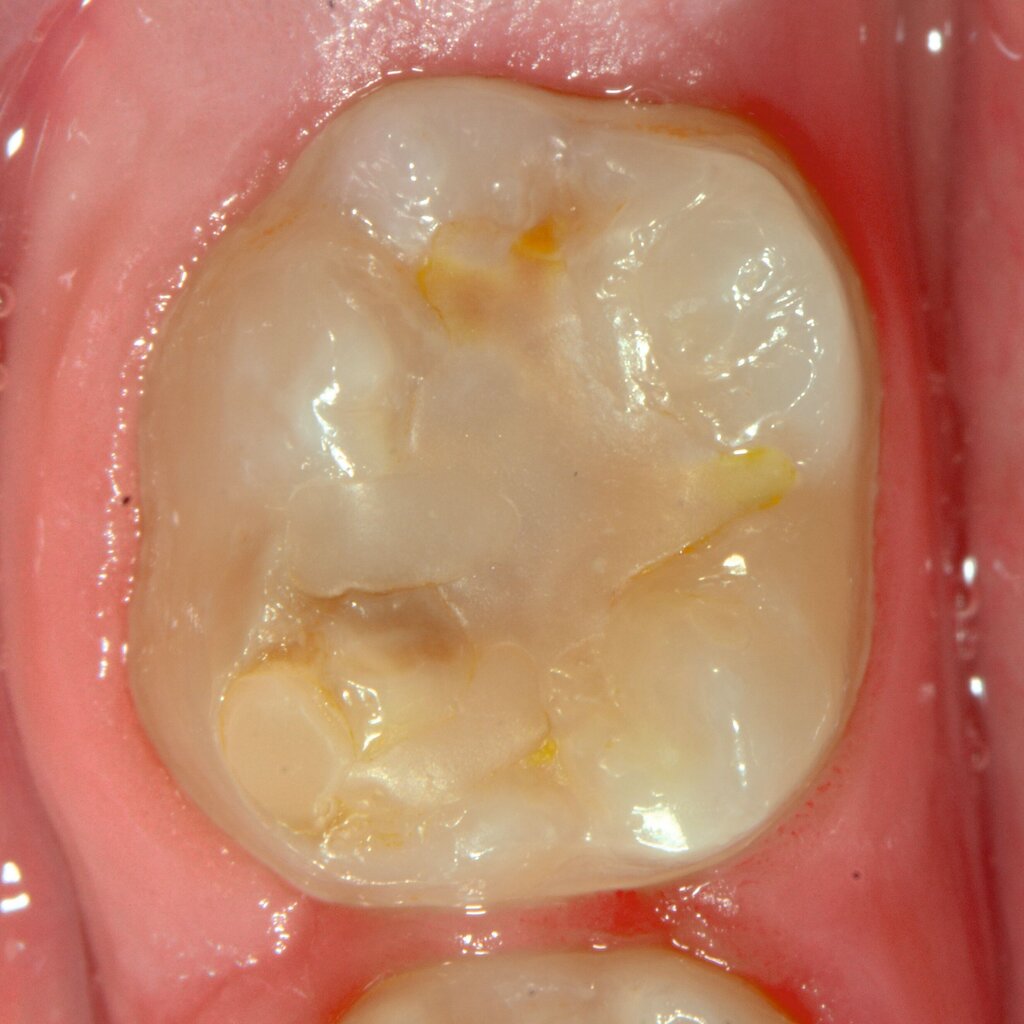

An umfangreich hypomineralisierten Zähnen können Schmelzeinbrüche (engl.: „enamel breakdown“ oder „enamel desintegration“, Abbildung 5) auftreten [Lygidakis et al., 2010; 2022]. Da diese oftmals die Folge einer fehlenden Belastungsfähigkeit des Zahnschmelzes sind und erst nach der Einstellung der Zähne in die Okklusion auftreten, werden sie auch als posteruptive Schmelzeinbrüche bezeichnet. Sie sind häufig im Bereich der Kauflächen beziehungsweise Höcker der Molaren zu finden, führen zur Dentinexposition und damit einhergehend zu ausgeprägten Hypersensitiven insbesondere bei Kindern, deren Zähne gerade erst durchgebrochen sind [Linner et al., 2021].

Frontzähne sind seltener von MIH-bedingten Schmelzeinbrüchen und Hypersensitivitäten betroffen. Von den posteruptiven Oberflächeneinbrüchen sind präeruptive Defekte abzugrenzen. Diese Zähne brechen bereits mit einem vorhandenen Oberflächendefekt in die Mundhöhle durch.

Bei post- beziehungsweise präeruptiven Oberflächendefekten ergibt sich in einigen Fällen die Indikation zur Restauration dieser MIH-Zähne. Unter Verweis auf die Lokalisation von MIH-bedingten Hypomineralisationen außerhalb der typischen Kariesprädilektionsstellen – zum Beispiel okklusale Fissuren und Grübchen oder Approximalflächen – werden diese als „atypische Restaurationen“ (engl.: „atypical restoration“, Abbildung 6) klassifiziert. Als ein weiteres Erkennungsmerkmal gilt die Präsenz von Hypomineralisationen im Bereich der Restaurationsränder. MIH- und kariesbedingte Restaurationen können und sollten sicher voneinander abgegrenzt werden.

Für die Dokumentation und Klassifikation der MIH wurden verschiedene Systeme vorgeschlagen. Als historisch und veraltet gilt der (modifizierte) DDE-Index. Demgegenüber haben die Kriterien der EAPD – abgegrenzte Opazitäten (Abbildung 3 und 4), Schmelzeinbrüche (Abbildung 5), atypische Restaurationen (Abbildung 6) – mittlerweile die weiteste Verbreitung gefunden. Diese wurden 2003 erstmals zur Beschreibung der MIH auf empirischer Basis publiziert [Weerheijm et al., 2003] und den Jahren 2010 und 2022 im Rahmen der damaligen MIH-Workshops bestätigt [Lygidakis et al., 2010; 2022].